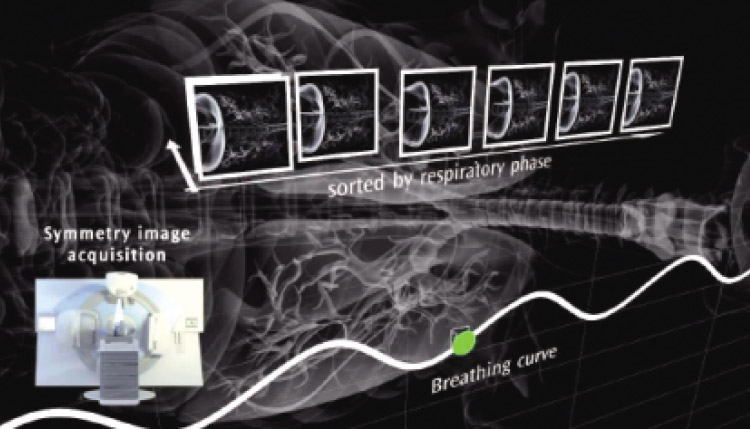

4D-CBCT(四次元コーンビームCT)

4DコーンビームCT機能(Symmetry)

呼吸運動のある臓器では、病変に集中した照射野を正確に照射することが難しくなります。4D-CBCTでは内臓器の動きまでリアルタイムに観察し、ビームの再現性を⾼めます。